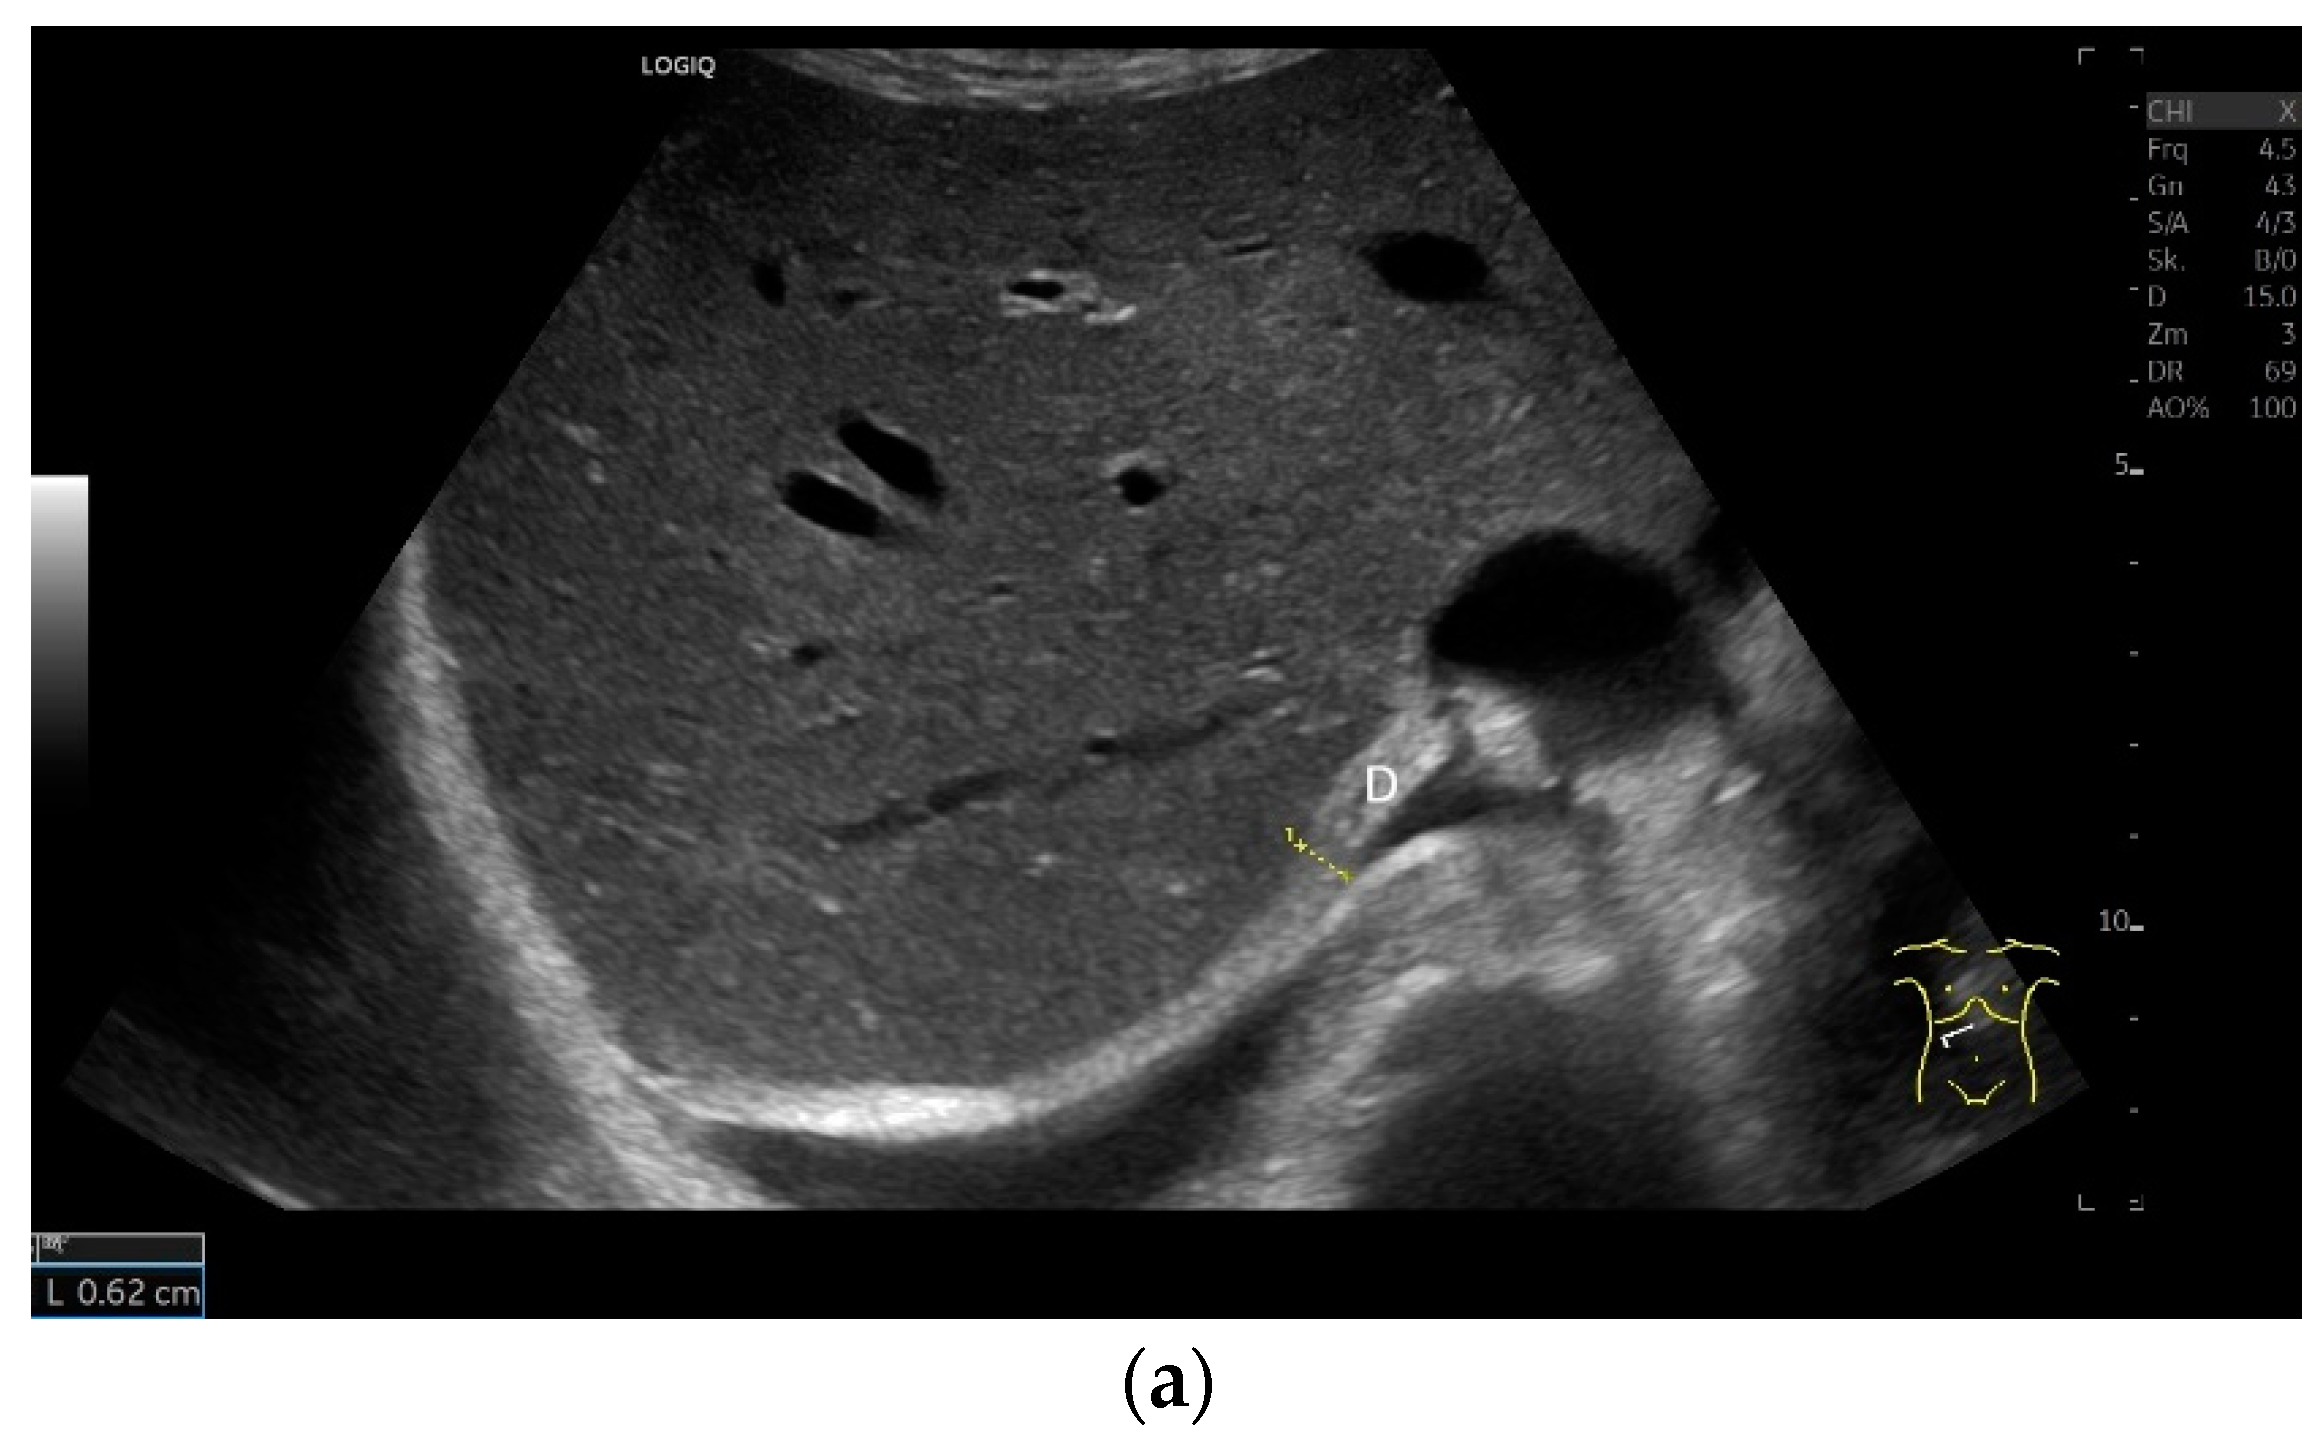

Regardless of the recommended positions for standardized measurements, the diaphragm can be viewed in other areas. This works quite well on the flank and subcostally in the midclavicular line (Figure 7).